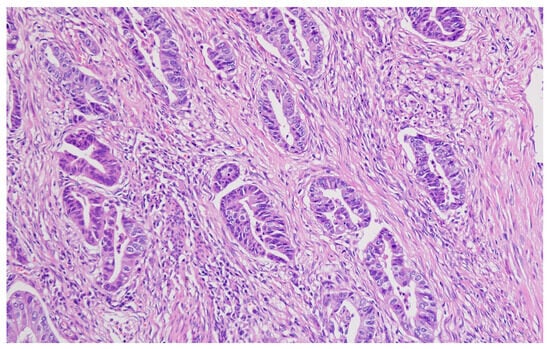

Hematoxylin–eosin staining was used for the direct exposure of the histopathologic subtypes (according to the WHO classification) present in the studied group, as shown in optical microscopy images.

Representative histopathological images of different tumor types are shown in Figure 2, Figure 3, Figure 4, Figure 5, Figure 6 and Figure 7, illustrating the histological subtypes observed in our cohort.

Figure 2. Tubular adenocarcinoma showing well-formed glandular structures with moderate nuclear atypia (H&E, ×200, scale bar = 100 μm).